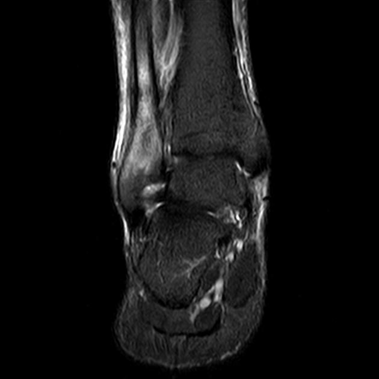

A 43-year-old female marathon runner presented with a stress fracture in the distal region of the fibula. She had been experiencing pain in her ankle for several weeks, and the pain had worsened recently. She was unable to run or walk without pain. The patient did not have any underlying osteometabolic pathologies and used an intrauterine device for contraception. She also underwent regular nutritional monitoring and maintained an adequate sleep schedule, which is crucial for bone health and overall recovery. X-rays and MRI confirmed the presence of a stress fracture.

The MRI showed significant edema and a clear fracture line in the distal fibula. Initially, she was placed in a walking boot and instructed to rest her leg, reducing weight-bearing activities to allow the bone to heal. After four weeks of rest, her pain had improved, but the fracture was not yet fully healed, as indicated by follow-up imaging. Given her active lifestyle and the need for a quicker recovery, the patient was started on teriparatide 20 mcg daily.

Her recovery was marked by a steady improvement in pain levels and functional outcomes, allowing her to resume her athletic activities with confidence. (Figure 1,2)